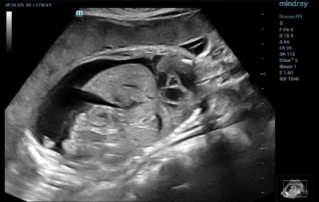

Ultrasound Journal 34 - Use of IOTA-ADNEX & O-RADS risk assessment models in MDT management of Adult Granulosa Cell Tumor

Comprehensive overview of granulosa theca cell tumors of the ovary, covering epidemiology, clinical presentation, diagnosis, treatment options, and prognosis for both adult and juvenile types.